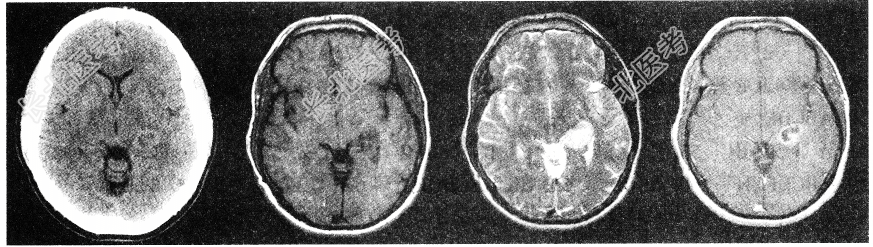

- 单项选择题男性患者,53岁。头晕, 偏盲,请结合影像图像选择最可能的诊断为

C、多形性恶性胶质瘤